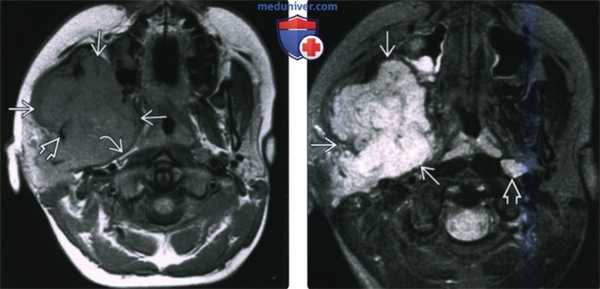

(Слева) На аксиальной МРТ (Т1ВИ) в жевательном пространстве визуализируется саркома Юинга в виде огромного объемного образования с гиперинтенсивным относительно мышц сигналом. Ветвь нижней челюсти разрушена, на этом изображении виден лишь ее мелкий фрагмент. Полоска окологлоточного жира смещена кнутри.

(Справа) На аксиальной МРТ (Т2ВИ FS) у этого же пациента определяется неоднородный сигнал крайне высокой интенсивности в опухоли. Хорошо различимый заглоточный лимфоузел слева является случайной находкой.г) Патология:

(Слева) КТ с КУ, аксиальная проекция. Злокачественная фиброзная гистиоцитома жевательного пространства и нижней челюсти. Солидная опухоль, которая умеренно накапливает контраст, располагается в правом жевательном пространстве и разрушает нижнюю челюсть, в том числе ее ветвь и тело. Жевательное пространство представляет собой глубокую область лица, в которой может возникать саркома.

(Справа) КТ с КУ, аксиальная проекция, тот же пациент. Солидная опухоль, умеренно накапливающая контраст, разрушает значительную часть нижней челюсти.2. КТ при саркоме жевательного пространства: